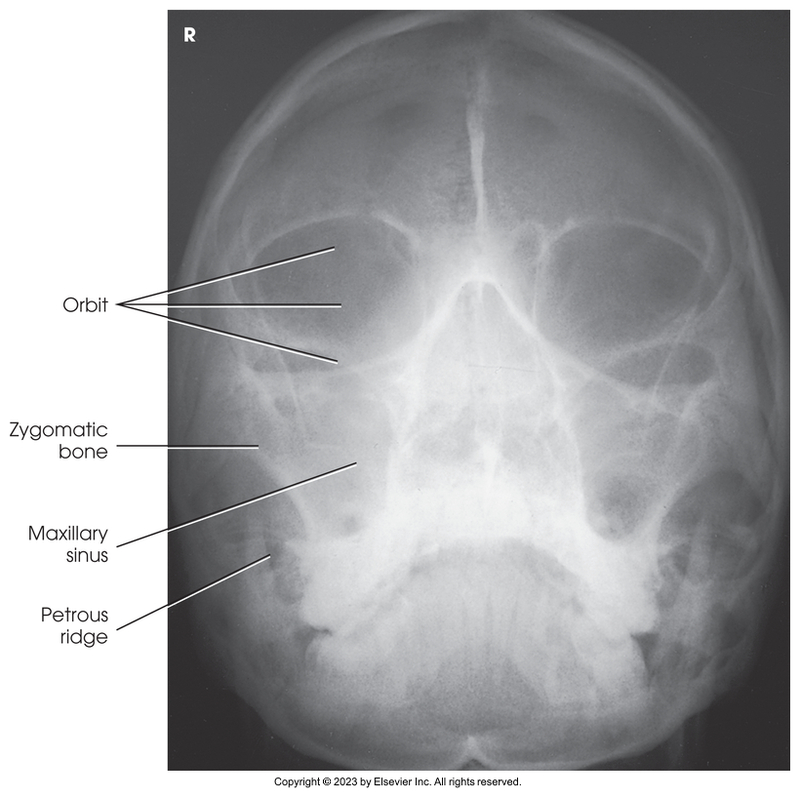

Parietoacanthial of the orbits - Modified Waters Method

Parietoacanthial of orbits - Modified waters method